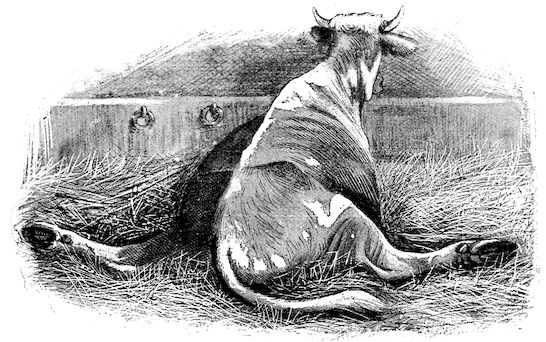

Fig. 1.—Rachitis in a young goat.

Fig. 1.—Rachitis in a young goat.